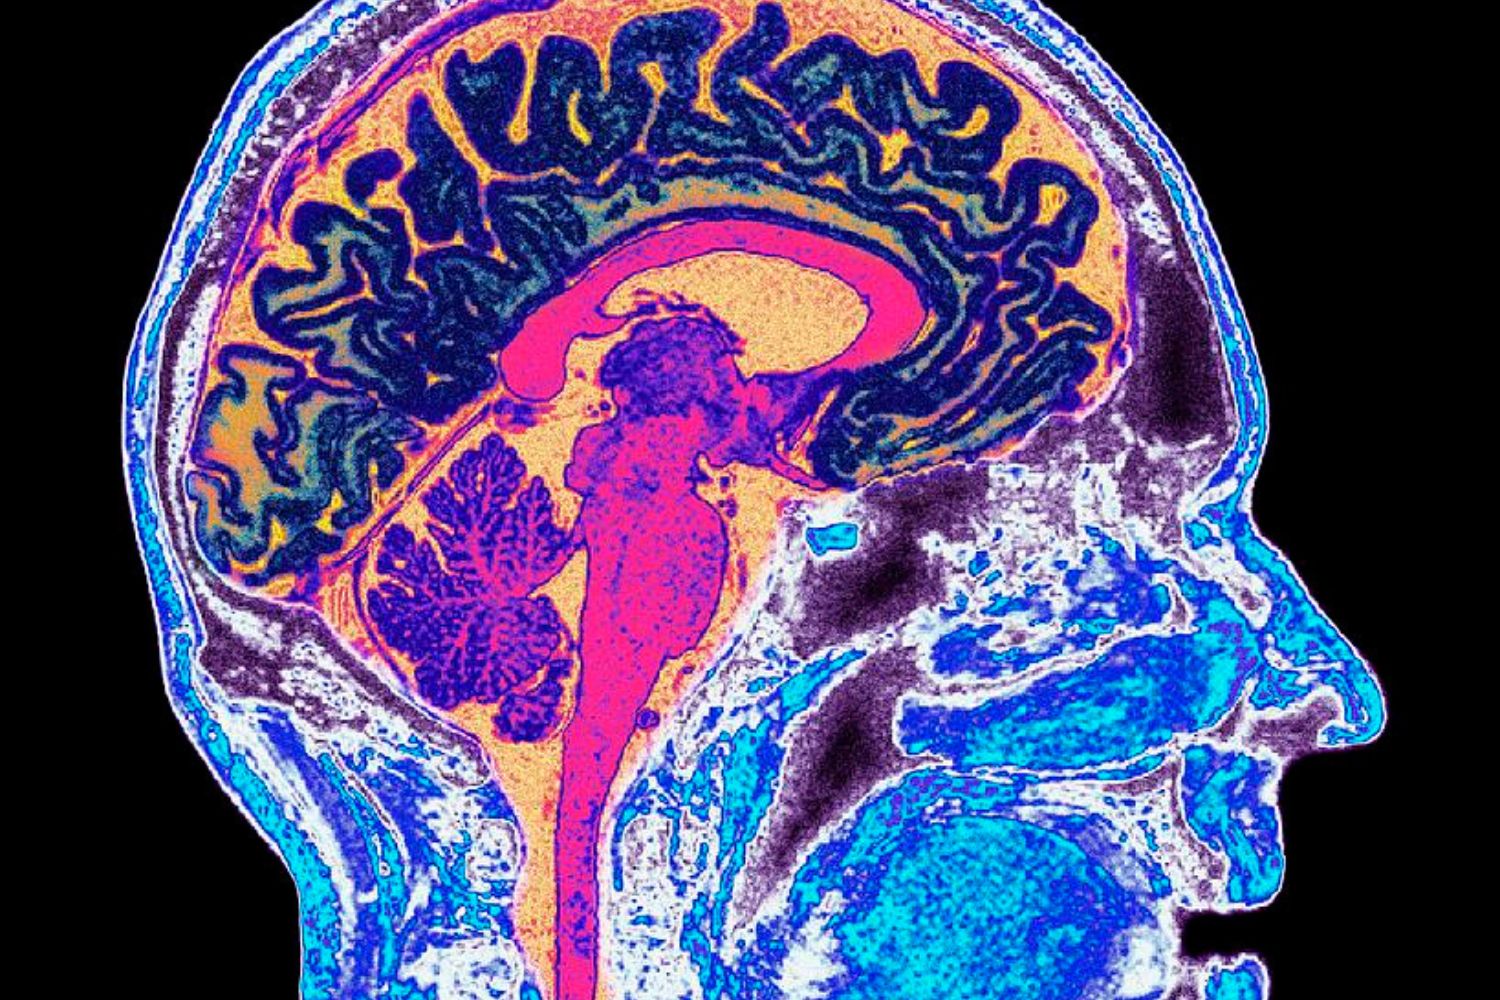

Durante décadas, o cérebro foi visto como um órgão com capacidade mínima de regeneração. Diferentemente de tecidos como a pele ou a córnea, ele tende a permanecer estável após lesões graves, com poucas chances de recuperação espontânea. Agora, um novo estudo publicado na revista Cell Stem Cell desafia essa visão ao mostrar que células-tronco podem ser “treinadas” para se integrar ao cérebro lesionado e restaurar conexões neurais perdidas após um acidente vascular cerebral (AVC).